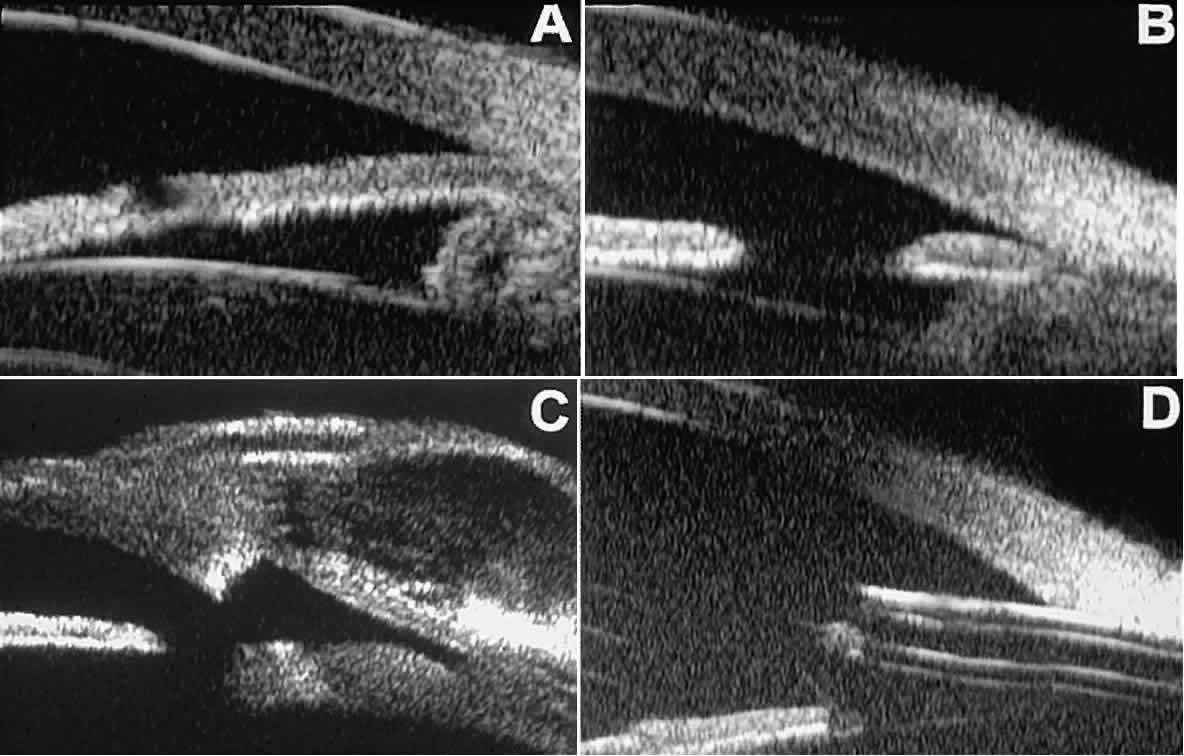

In eyes with a narrow angle, UBM shows the extent of angle closure, reveals

the depth of the anterior and posterior chambers, and identifies

pathologic processes pushing the lens and iris forward (Fig. 11).2–4,8 UBM has been able to differentiate between primary angle closure (i.e., cases of angle closure without additional pathology responsible for the

anterior lens-iris displacement [see Fig. 11A] and secondary angle closure due to processes such as lens swelling

and dislocation (see Fig. 11B), massive hemorrhagic retinal detachment pushing the lens and iris anteriorly (see Fig. 11C), and multiple neuroepithelial cysts of the iridociliary sulcus (see Fig. 11D).  Fig. 11. Angle configuration in eyes with angle-closure glaucoma. A. Primary angle-closure glaucoma with anterior displacement of lens and

iris. B. Angle closure secondary to swollen, cataractous lens (phakomorphic angle

closure). C. Angle closure secondary to massive hemorrhagic retinal detachment; the

subretinal blood is evident in the lower right corner of the photograph. D. Angle closure secondary to multiple peripheral iris cysts. Fig. 11. Angle configuration in eyes with angle-closure glaucoma. A. Primary angle-closure glaucoma with anterior displacement of lens and

iris. B. Angle closure secondary to swollen, cataractous lens (phakomorphic angle

closure). C. Angle closure secondary to massive hemorrhagic retinal detachment; the

subretinal blood is evident in the lower right corner of the photograph. D. Angle closure secondary to multiple peripheral iris cysts.

|

Postoperative UBM imaging of the anatomic changes caused by glaucoma surgery

often helps to explain mechanisms of success and failure of the

various surgical procedures (Fig. 12).3,4 After laser iridotomy, UBM can show whether the iridotomy is partial thickness (see Fig. 12A) or full thickness (see Fig. 12B) and whether the plane of curvature of the peripheral iris has changed

compared with the pretreatment findings. After trabeculectomy (see Fig. 12C), UBM can show whether the scleral aperture is patent or blocked internally, whether

the peripheral iridectomy is open or blocked, and whether

the filtering bleb is flat, shallow, or deep.9 After tube shunt surgery (see Fig. 12D), UBM can show the position of the tip of the tube and whether its orifice

is open or plugged.  Fig. 12. UBM features in glaucomatous eyes after treatment or filtering surgery. A. Incomplete peripheral iridectomy created by laser. B. Full-thickness peripheral iridectomy created by laser. C. Postoperative features of trabeculectomy including peripheral iridectomy, inner

scleral defect, thin residual scleral flap, and overlying conjunctival

filtering bleb. D. Tube shunt projecting radially into anterior chamber; note that the tube “shadows” deeper structures. Fig. 12. UBM features in glaucomatous eyes after treatment or filtering surgery. A. Incomplete peripheral iridectomy created by laser. B. Full-thickness peripheral iridectomy created by laser. C. Postoperative features of trabeculectomy including peripheral iridectomy, inner

scleral defect, thin residual scleral flap, and overlying conjunctival

filtering bleb. D. Tube shunt projecting radially into anterior chamber; note that the tube “shadows” deeper structures.

|